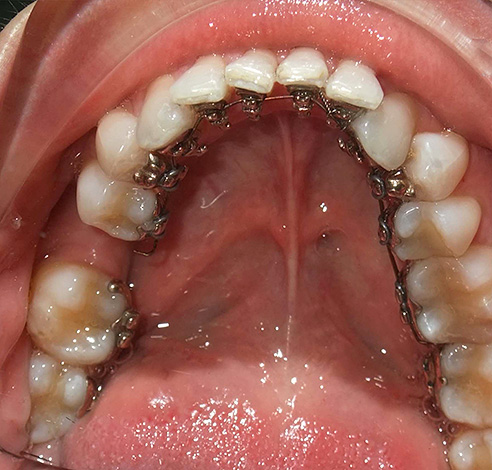

La foto sotto mostra le parentesi graffe dello zaffiro:

La prima opzione: sistemi di staffe linguali - l'ortodontista li attacca ai denti dal palato e dalla lingua, e quindi le persone intorno non sospettano che la persona indossi le parentesi graffe.

Esistono due varietà di tali sistemi: apparecchi linguali standard, i cosiddetti sistemi 2D. Sono prodotti dalla fabbrica, hanno forma e dimensioni standard, sono in grado di spostare i denti in uno spazio bidimensionale. Il medico lega l'arco che sposta i denti alle serrature con legature di metallo o di gomma.